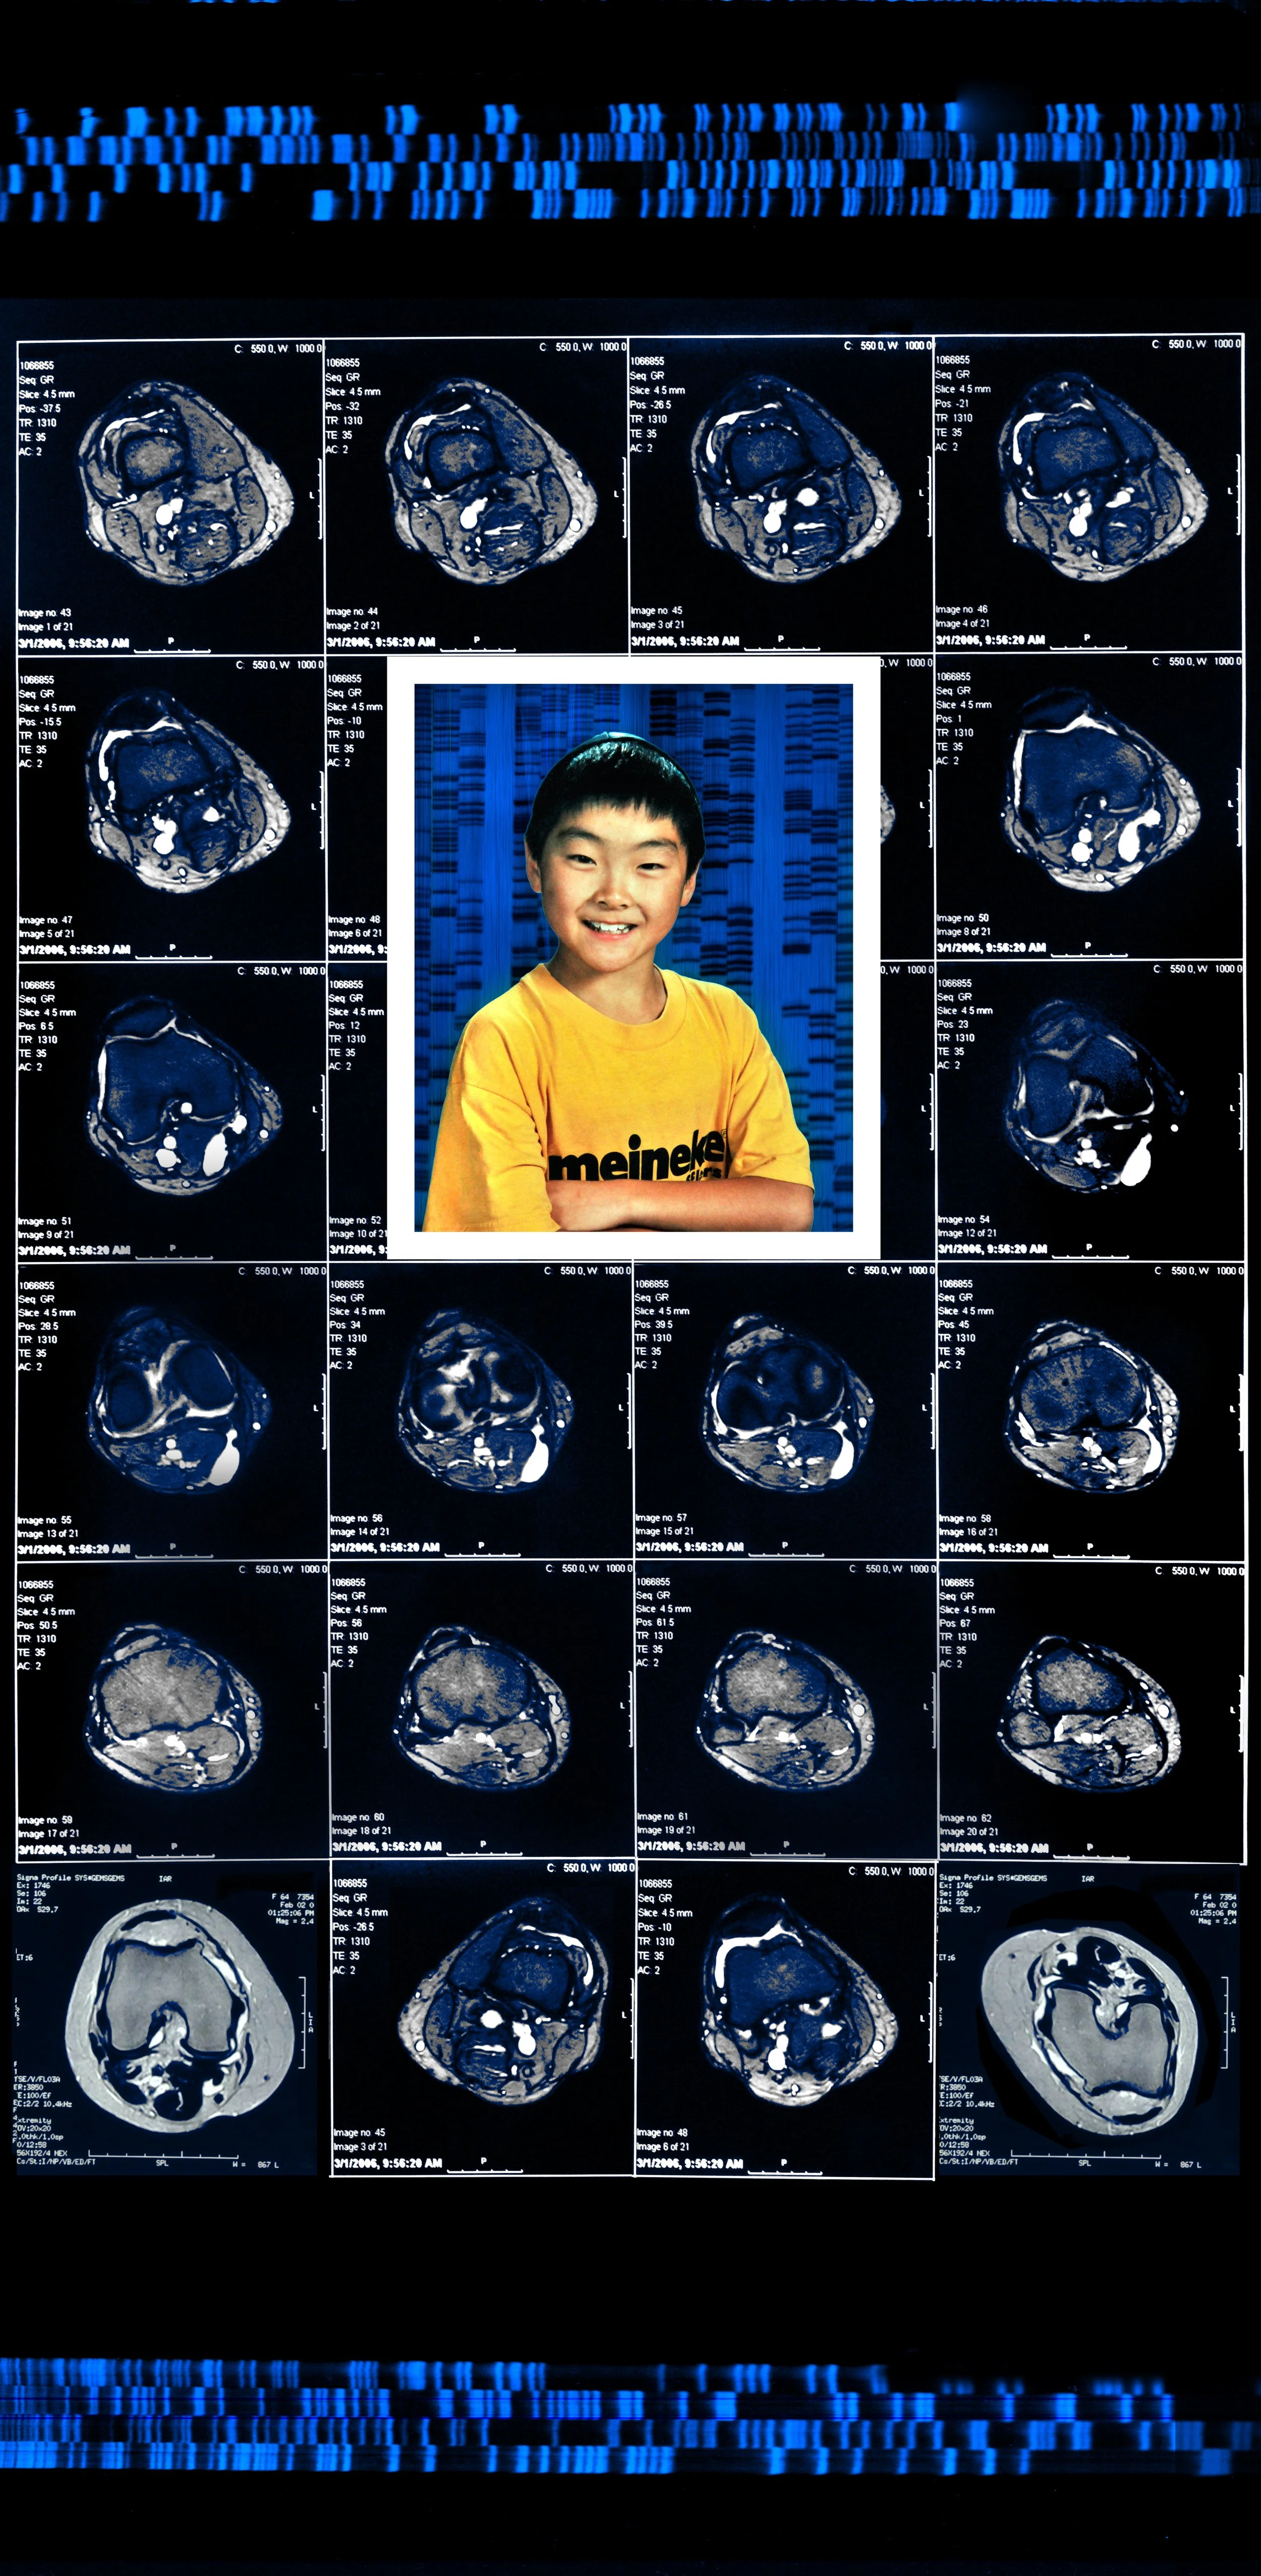

Comprising eight 47” x 23” backlit Plexiglas panels, each work features a portrait, often of individuals from diverse racial, ethnic, and cultural backgrounds. Surrounding these portraits are embedded CT scans, MRIs, and DNA sequencing gels. These medical images, reimagined as expressive symbols, evoke biological inheritance, invisible histories, and interior experience rather than clinical diagnosis.

Used metaphorically, DNA strands suggest ancestral continuity; CT scans and MRIs hint at the unknowable workings of body and psyche; ghostly anatomical forms recall trauma, resilience, and emotional scars. By pairing portraiture with interior imaging, the series questions how we perceive identity. Are we defined by surface appearance—skin, gender, dress—or by memory, genetics, and lived medical experience? Can scientific data be truly neutral, or does it reflect cultural bias and interpretation?

Asian Boy 47” x 23”